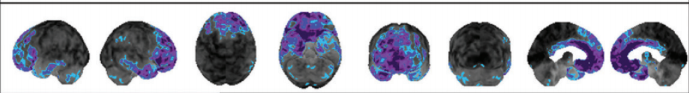

lewy body dementia